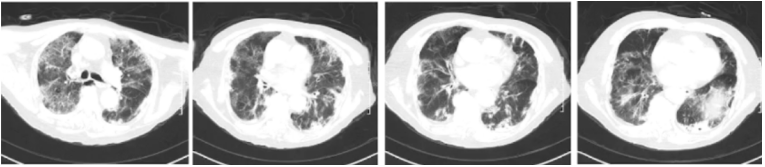

加用巴瑞替尼后患者病情稍有好转,能间断脱离无创呼吸机,改为鼻导管吸氧,呼吸频率25~30次/min,查体可闻及肺部散在细湿啰音。2023年1月13日床边胸片提示双肺间质性改变,较前有所吸收(图3)。1月19日复查胸部CT提示:肺气肿合并间质性改变,考虑病毒性肺炎趋于平稳期(图4)

图3  床边X线胸片(2023-01-13)

图4  复查胸部CT(2023-01-19)